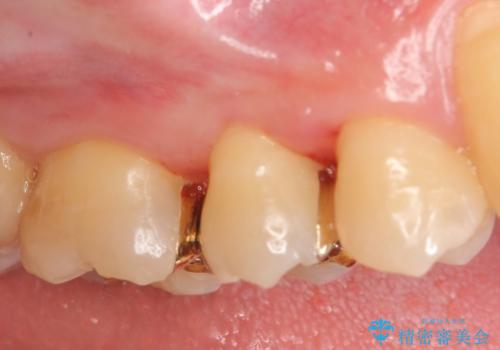

- 19万円(ゴールドインレー×2 セラミックインレー×1)費用は治療当時の料金となります

セラミック・ゴールド共に化学的な変化が少なくインレー素材として理想的ですが、色調や強度・加工のしやすさ・最低限必要な厚み等の条件が異なります。

今回の治療では、虫歯を除去したのちより修復に適した素材を選択することで歯を削る量を可及的に少なくすることと、長期的な予後を期待できるような状態にすることができました。